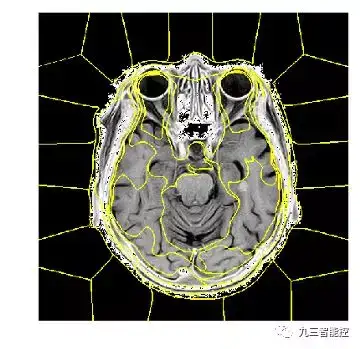

超像素(Super Pixel)

超像素(SuperPixel),就是把原本多个像素点,组合成一个大的像素。超像素由一系列位置相邻且颜色、亮度、纹理等特征相似的像素点组成的小区域。这些小区域大多保留了进一步进行图像分割的有效信息,且一般不会破坏图像中物体的边界信息。